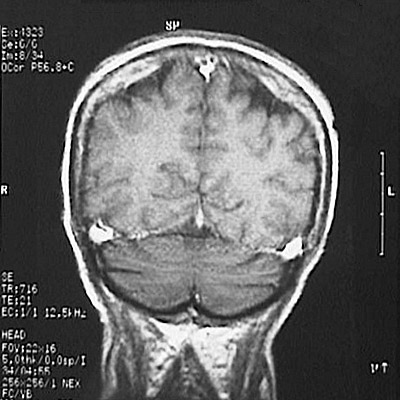

This is a normal coronal T1 weighted enhanced MRI scan demonstrating the occipital lobe and cerebellar hemisphere and superior sagittal sinus and inferior sagittal sinus and transverse sinus and tentorium cerebelli.